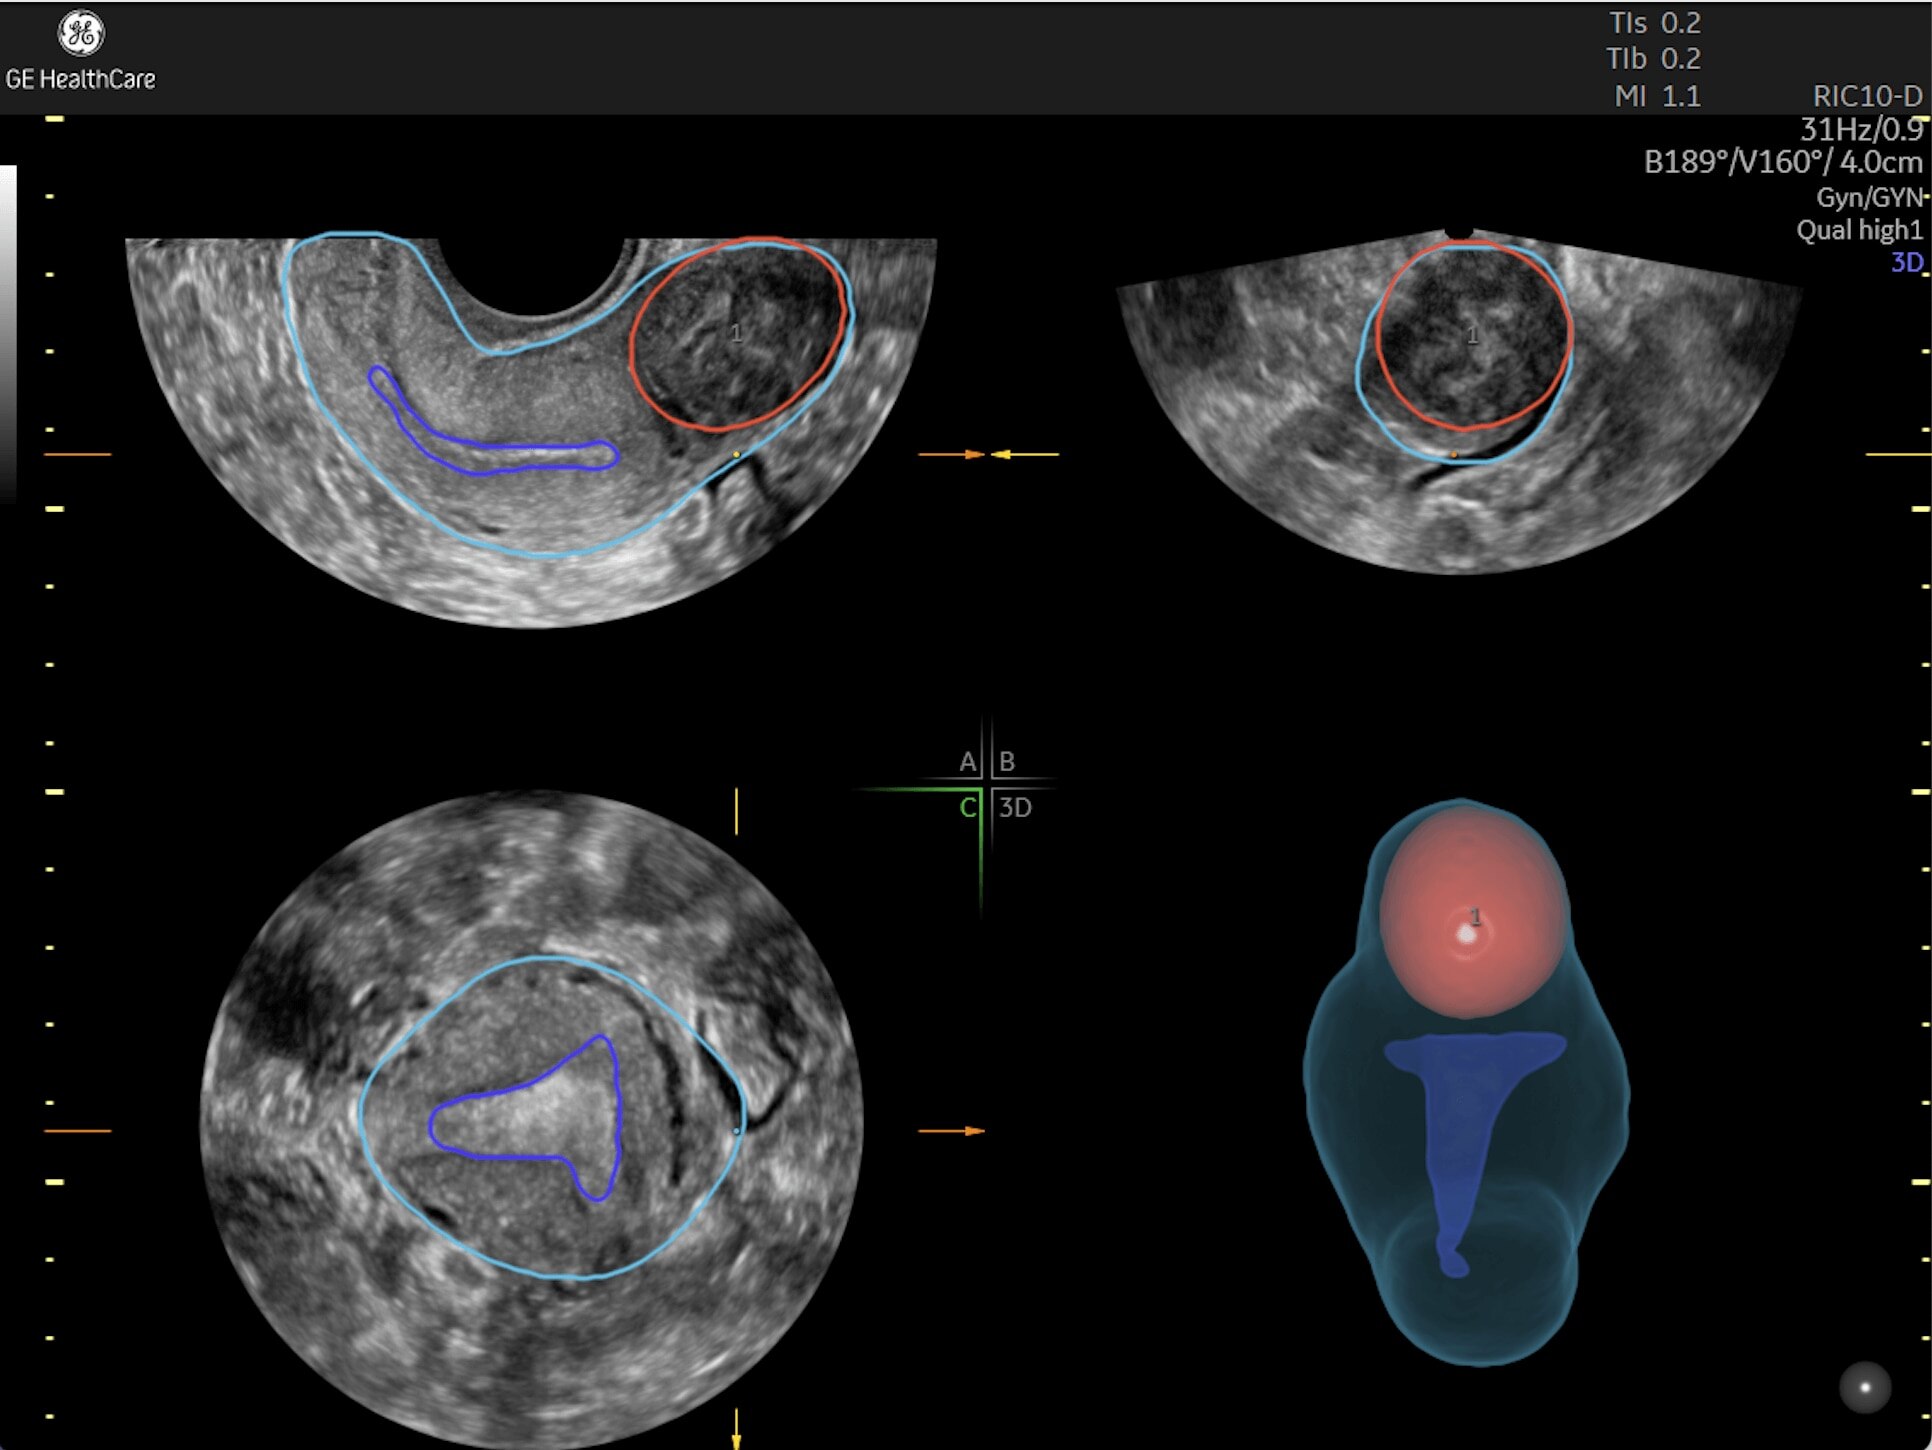

Generate spectacular 2D/3D and color Doppler images with increased penetration and stunning clarity, to help visualize critical details needed for diagnostic assurance. The Lyric Architecture unlocks new imaging and processing power to expand your imaging capabilities for years to come

Experience a new level of efficiency with the highly intuitive and customizable ultrasound that promotes progress and productivity. Leverage the power of artificial intelligence and easy-to-use automation tools that streamline workflows and make a real impact every day.